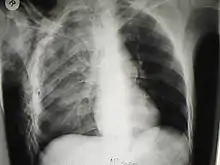

الصدر السائب هي حالة طبية مهددة للحياة تحدث عندما يتعرض جزء من القفص الصدري للكسر تحت تأثير ضغط كبير، ويصبح هذا الجزء غير متصل بجدار الصدر. تحدث عندما يتعرض العديد من الأضلاع المتجاورة للكسر في أماكن متعددة، ينفصل جزء، فيصبح هناك جزء من جدار الصدر يتحرك بشكل مستقل. عدد الأضلاع التي يجب أن تكون كسرت تختلف حسب اختلاف التعريفات: بعض المصادر تقول انه يجب على الأقل أن يكسر ضلعين متجاورين في مكانين مختلفين،[1] وبعضها يتطلب كسر ثلاثة ضلوع أو أكثر وفي مكانين مختلفين أو أكثر.[2] يتحرك الجزء السائب في الاتجاه المعاكس لباقي أجزاء جدار الصدر: و ذلك لأن الضغط المحيط بالمقارنة مع الضغط داخل بالرئتين، فيدخل للداخل بينما باقي أجزاء الصدر تخرج للخارج، والعكس صحيح. وهذا يقال له "تنفس تناقضي""[3][4] يزيد من العمل والألم المحتاج لعملية التنفس. اكتشفت الدراسات أن أكثر من نصف المصابين بالصدر السائب يتوفون.

الصدر السائب مصحوب بشكل دائم بكدمة رئوية، جزء من أنسجة الرئة سوف تتداخل مع الاكسجين في الدم.[5] غالباً، الكدمة هي السبب في الفشل التنفسي والإصابات المتعددة، وليس الجزء السائب.[6]

حركة الاضلاع المستمرة في الصدر السائب في منطقة الكسر شديدة الألم، وليس لها علاج، والحواف الحادة للاضلاع المكسورة غالبا تحدث ثقب في الكيس الجنبي والرئتين وقد تسبب استرواح الصدر. القلق حول الرفرفة المنصفية (تغير المنصف مع الحركة التناقضية للحجاب الحاجز) لا تظهر لتكون مستحقة (ولذلك لا يؤخذ بها).[8] الكدمة الهوائية شائعة مع الصدر السائب وقد تسبب توقف التنفس. وهذا بسبب الحركة التناقضية للاجزاء المصابة التي تقاطع التنفس الطبيعي وحركة الصدر. الحركة التناقضية الطبيعية مرتبطة بتصلب الرئة، مما يجعلها تتطلب عمل اضافي للتنفس الطبيعي، ويزيد من مقاومة الرئة،[9] مما يصعب تدفق الهواء.[10] توقف التنفس بسبب الصدر السائب يتطلب تنفس اصطناعي والبقاء لمدة أطول في وحدة العناية المركزة. الضرر الملحوق بالرئتين في الصدر السائب هو السبب المهدد للحياة.